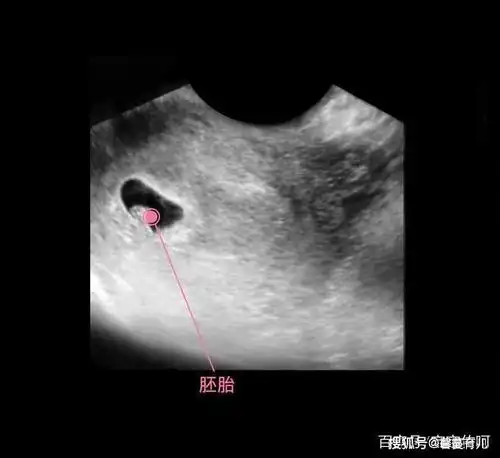

怀孕十二周可以从b超中的小肿块分辨男女,这真的可以看出来吗?

胎儿从卵泡到性别形成17张图片清晰诠释男宝女宝看得很清楚